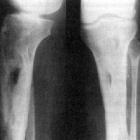

Сам имплант очень похож на некий титановый шуруп, который «вкручивают» в костную ткань челюсти. Внутри импланта есть резьба, в которую впоследствии вставится абатман – головка, фиксирующаяся винтом. Это произойдет после того, как импант приживется в десне, срастется с костью. На абатман уже устанавливают керамическую коронку. Сам имплант ставится очень быстро, примерно 20 минут. По вполне понятным причинам, окончание формирования зуба наступит не ранее, чем через 3-6 месяцев, это зависит от индивидуальных физиологических особенностей пациента.